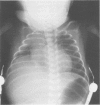

The clinical features of 14 neonates with congenital myotonic dystrophy were retrospectively reviewed. These babies represent all the new cases of congenital myotonic dystrophy seen in this department since 1982. Twelve babies were referred because of either difficulties in diagnosis or difficulties in the management of their respiratory problems. Of the 14 babies, 13 had birth asphyxia, 11 were premature, and four had intrauterine growth retardation. Ten babies required artificial ventilation from birth. Abnormalities on chest radiography included thin ribs (n =9) and raised right hemidiaphragms (n = 5). Recurrent episodes of collapse and consolidation of the lungs secondary to poor swallowing occurred in all ventilated babies. All babies ventilated for longer than four weeks died of respiratory complications before the age of 15 months. One baby was successfully extubated after diaphragmatic plication, but he died a few months later. Duration of ventilation was the best guide to prognosis.